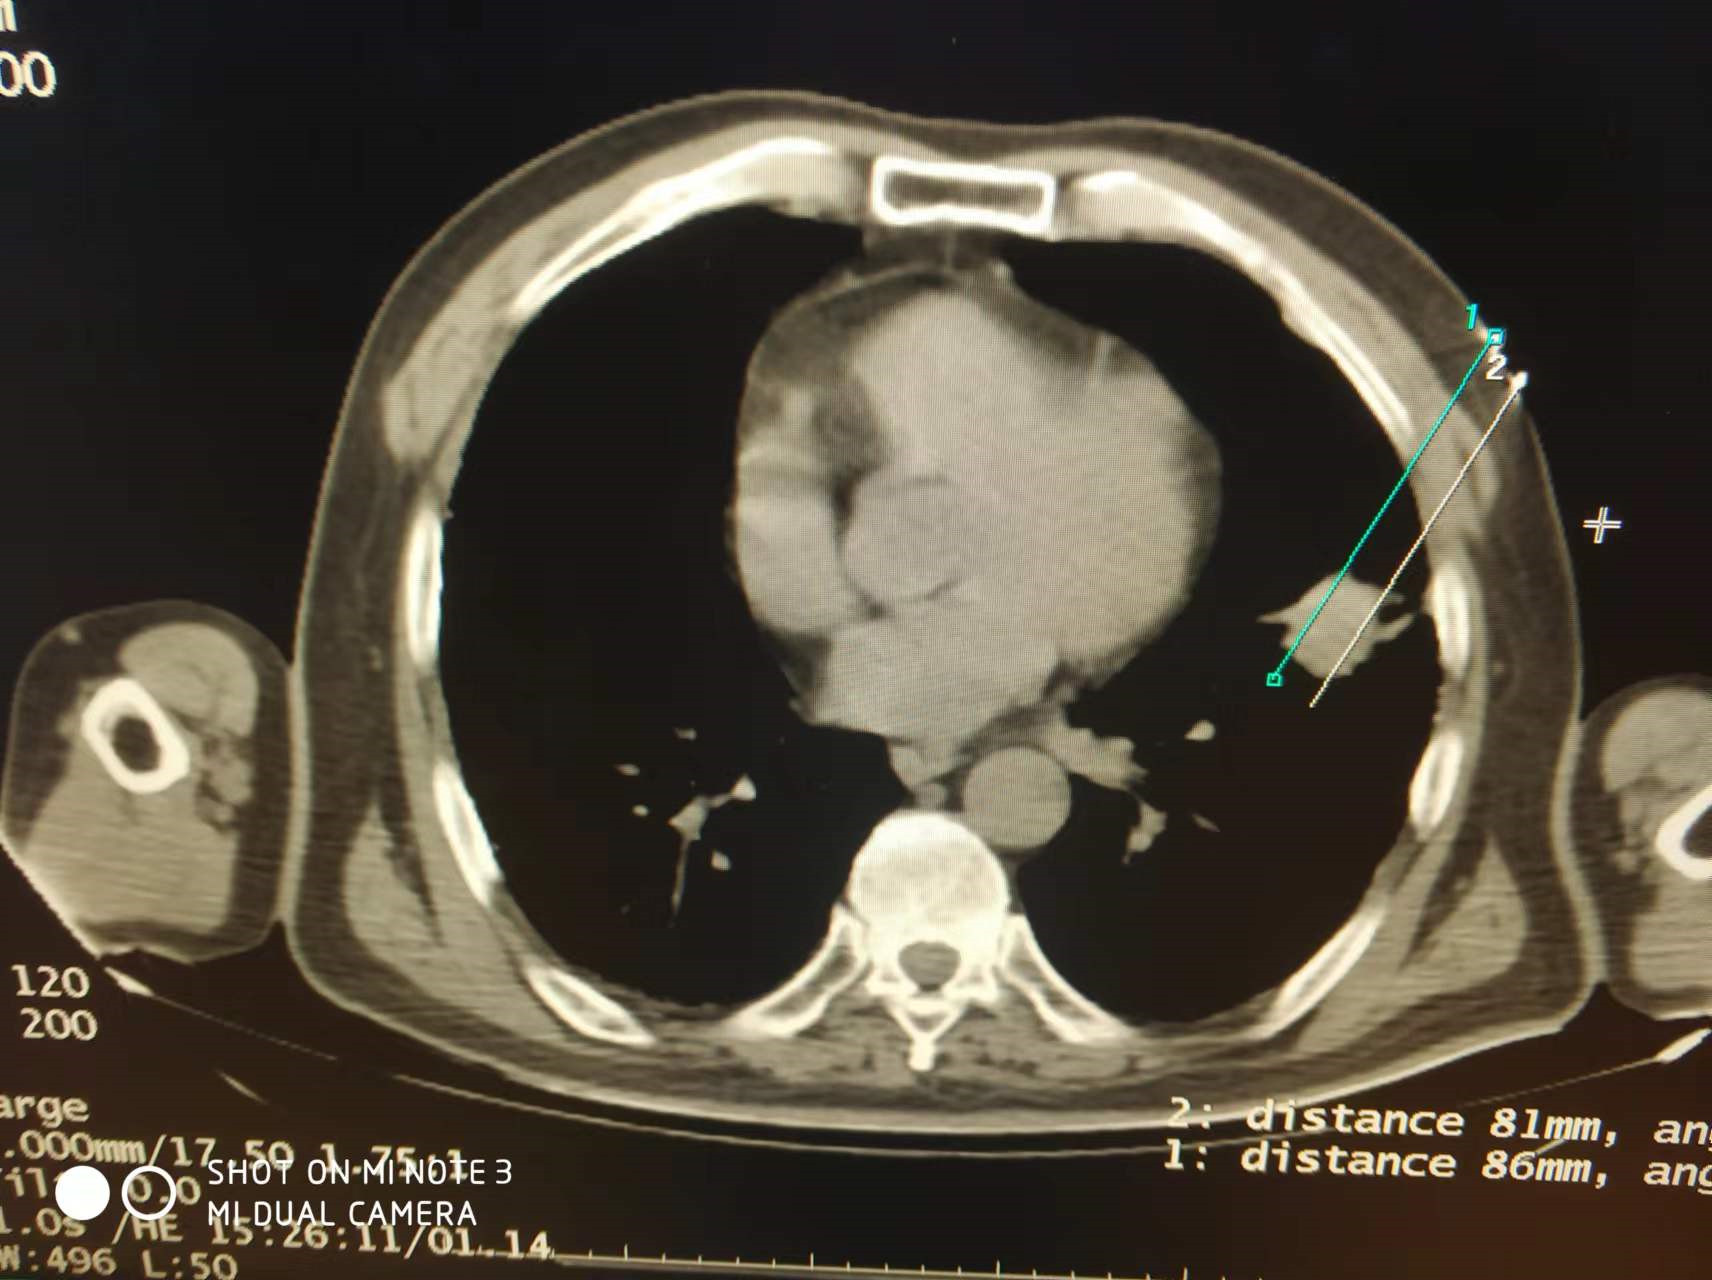

上一篇:2022年4月份肺部氩氦刀手术